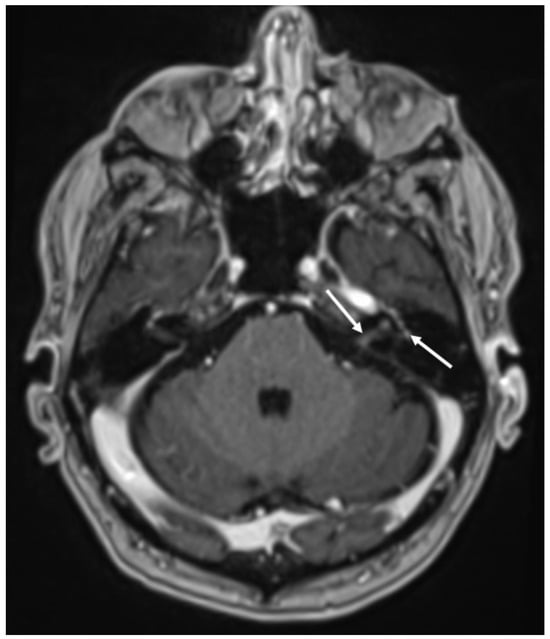

| Varicella Zoster Virus | • Leptomeningeal enhancement • Cerebellitis |

- Labin, E.; Tore, H.; Alkuwaiti, M.; Streib, C. Teaching Neuro Images: Classic Ramsay Hunt syndrome and associated MRI findings. Neurology 2017, 89, e79–e80. [Google Scholar] [CrossRef] [PubMed]

- Letchuman, V.; Donohoe, C.D. Brainstem and Cerebellar Involvement in Ramsay Hunt Syndrome. Case Rep. Otolaryngol. 2019, 2019, 7605056. [Google Scholar] [CrossRef] [PubMed]